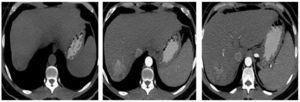

En agosto 2011, se realiza quimioembolización presentando respuesta parcial en el estudio de seguimiento a 3 meses. Se realizó QEIA nuevamente en diciembre 2011 (fig. 2). En seguimiento, se observa zona de captación en la periferia del tumor, en territorio subdiafragmático (fig. 3); en marzo del 2012 se decide realizar nueva QEIA. Por la localización de la zona con actividad, se realiza angiografía selectiva de probables ramas accesorias. En angiografía previa a la embolización, se identifica irrigación de la zona de actividad por parte de la arteria frénica derecha (fig. 4). Se realiza embolización blanda y ablación por radiofrecuencia (ARF). Última resonancia magnética dinámica de abril 2013, sin evidencia de activad tumoral (fig. 5).

Figura 2. Angiografía y QEIA a través de la arteria hepática derecha desde el tronco celíaco. Se observa captación del lipiodol y cisplatino por parte del tumor. Se identifica un defecto en la porción superior y lateral de la lesión.

Figura 4. Angiografía previa a la embolización de la enfermedad residual. Se observa ausencia de irrigación por parte de la arteria hepática, e irrigación del tumor por parte de la arteria frénica derecha.